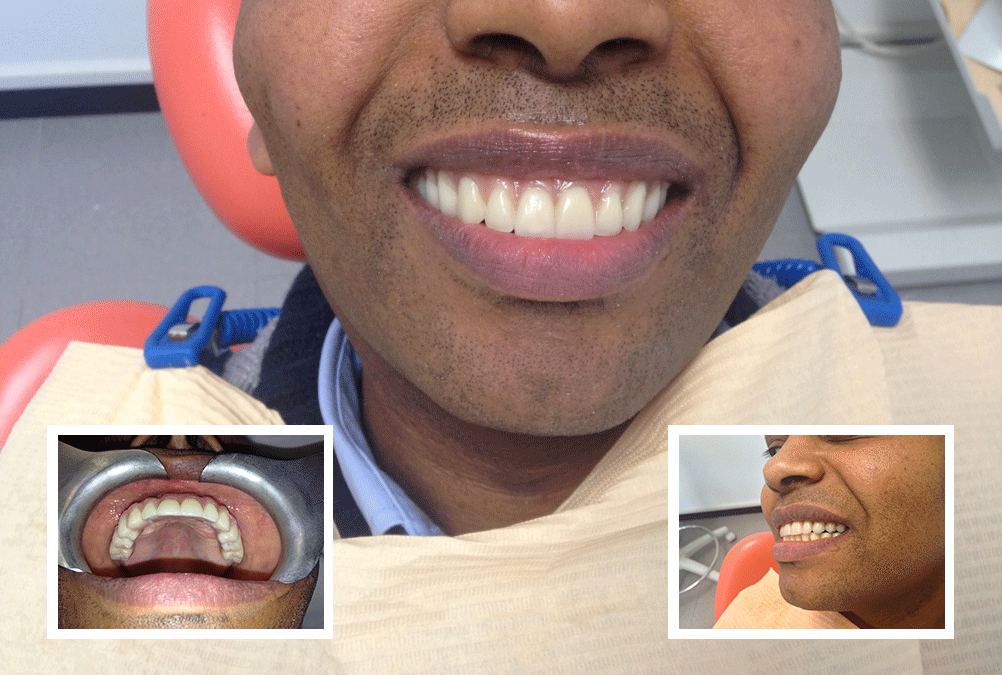

Intervento e consegna Protesi Definitiva Fissa – Tutto nella stessa seduta –

In un’unica seduta al paziente sono stati posizionati quattro impianti (tecnica All On Four) e inserita la nuova protesi fissa definitiva, avvitata sui nuovi quattro impianti.